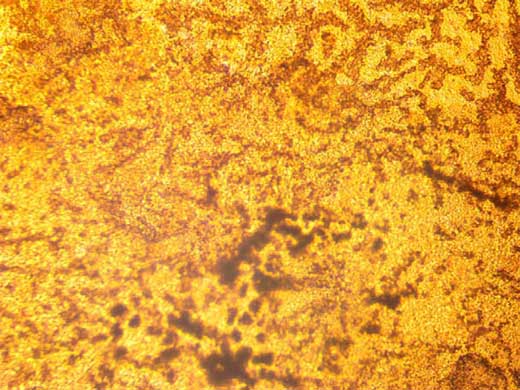

Análisis Histológico: Plasma Pobre en Plaquetas Gelificado. Visualizamos cúmulos de material fibrilar coagulado sobre una base amorfa.